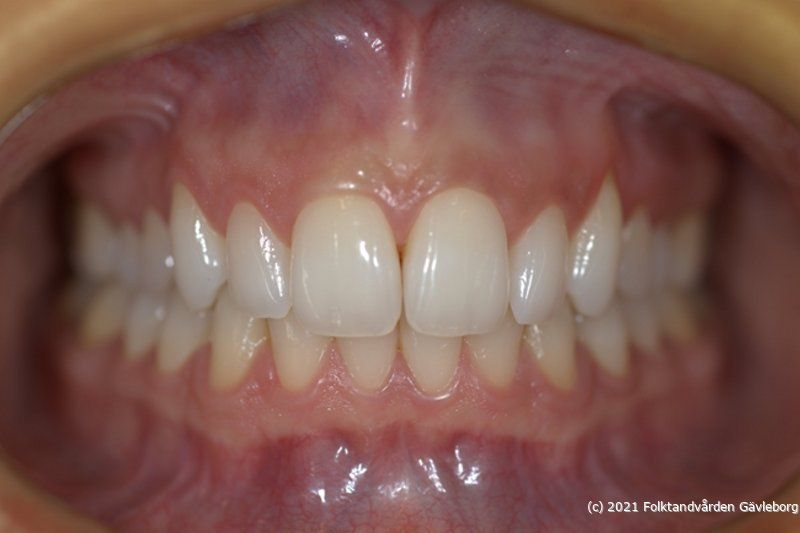

• Front i ocklusion (IP), höger och vänster sida. Avstånd ca 0,5 m

• io02Frontal

Hjälpmedel: Dubbeländad munvinkelhållare. Samma inställning mellan front / höger / vänster sida = samma bildskala!